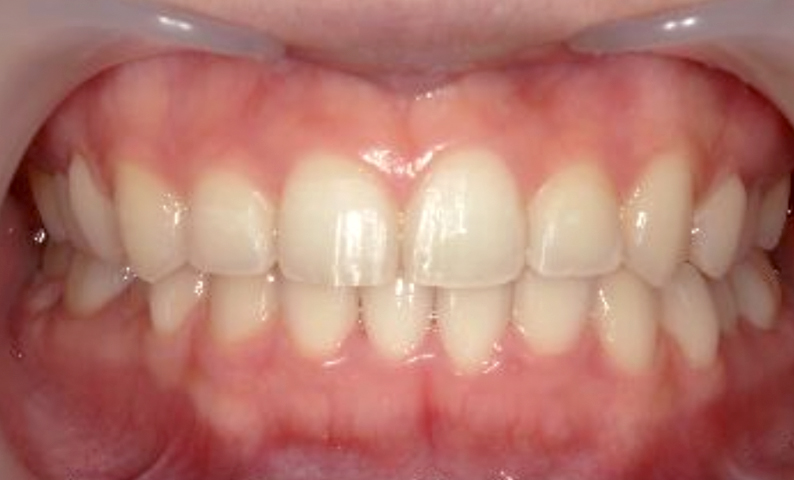

症例_001 上下顎の部分矯正

治療期間:12ヶ月金額:54万円+税女性前歯のガタガタ逆八の字